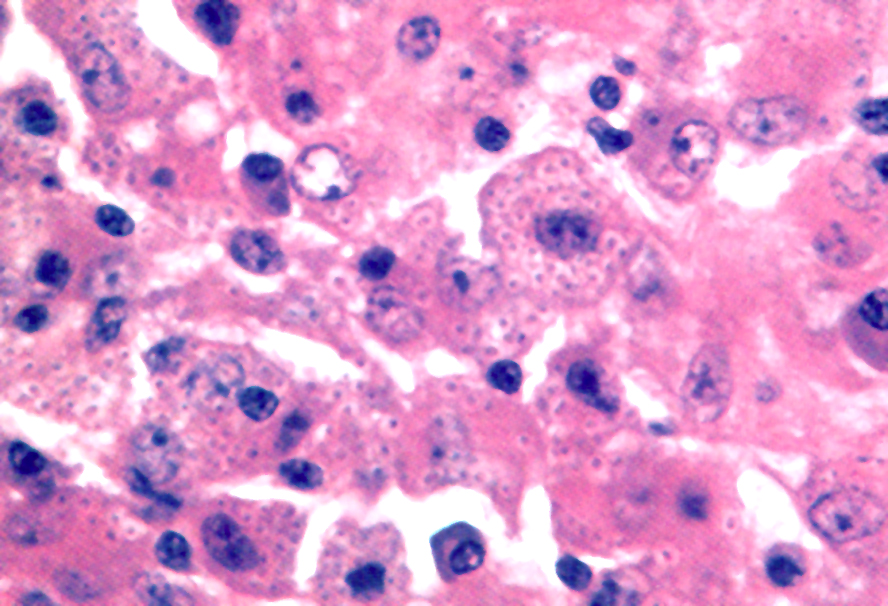

Microscopic (histologic) description

- Either multiple small epithelioid granulomas or huge epithelioid granulomas with prominent Langhans giant cells and central necrosis (J Clin Pathol 1988;41:93)

Microscopic (histologic) images

Contributed by Mark R. Wick, M.D.